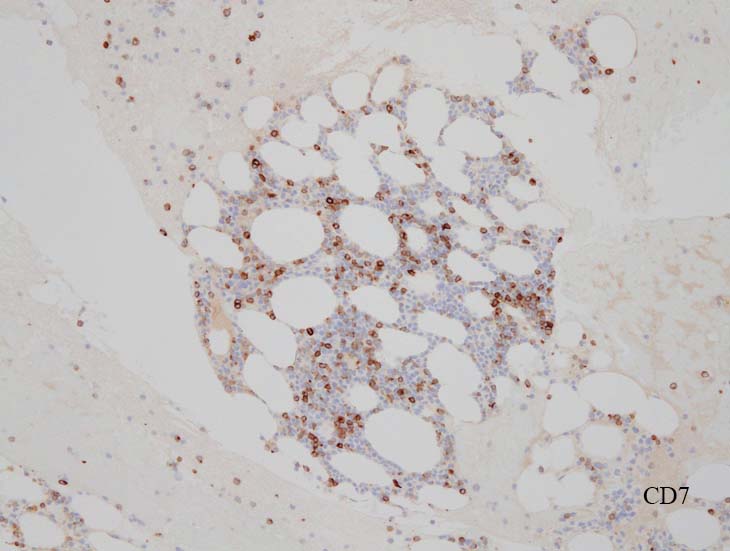

blastic cellsは, CD45+, CD34+, CD38+, TdT+, CD7+, HLA-DR+, CD123+. cCD3-, sCD3-(FCM), CD20-, CD19-とCD79a-(?) (plasma cellが陽性でIHCでは判定が難しい), MPO-.

CD3-, CD79aは増加しているplasma cellsが陽性で判定が難しい. CD10-, MPO-. (CD10は画像欠)